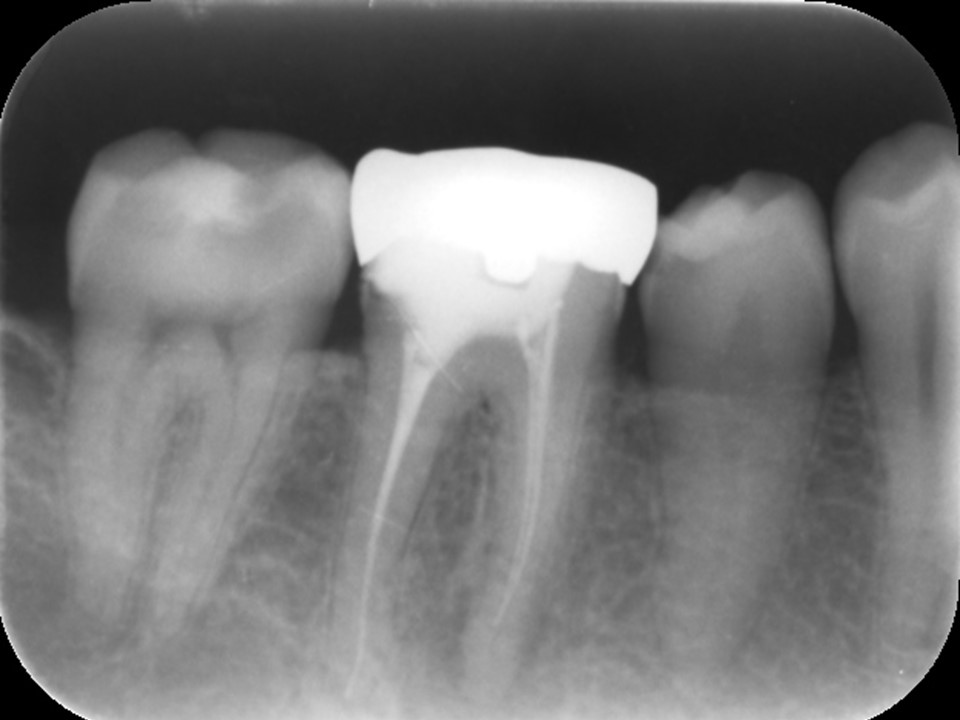

初診時レントゲンおよびCT画像です。すでに根管治療はされているが、根尖まで薬が入っておらず、根尖病変と思われる黒い透過像を認めます(矢印)

以前に行った根管治療が不十分であったためにバクテリアが繁殖し、根尖部が化膿して病変を生じている状態でした。(下写真)